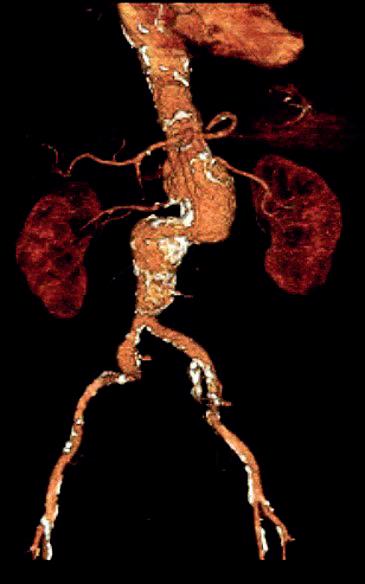

OUR PATIENT IS AN 80-YEAR-OLD male with significant comorbidities of coronary artery disease with previous coronary artery bypass graft surgery, hypertension, chronic obstructive pulmonary disease, atrial fibrillation, and a body mass index (BMI) of 37kg/m2, presenting with a 7cm type IV thoracoabdominal aortic aneurysm based upon Centerline software (Centerline Biomedical). The bilobular suprarenal and infrarenal aneurysm is noted to be tortuous with mural thrombus at the level of the paravisceral vessels (Figure 1). Therefore, the plan was endovascular intervention with a staged thoracic endovascular aortic repair (TEVAR) and four-vessel branched fenestrated physician-modified endovascular graft (PMEG) endovascular aneurysm repair (EVAR). The patient’s index operation was performed with a TEVAR one-piece Zenith Alpha (Cook Medical) 36x32x161mm under moderate sedation. The endograft was landed proximally just distal of the left subclavian artery and distally about 5.5cm above the celiac artery. The patient tolerated the procedure well and was discharged the following day.

Figure 1. The bilobular suprarenal and infrarenal aneurysm